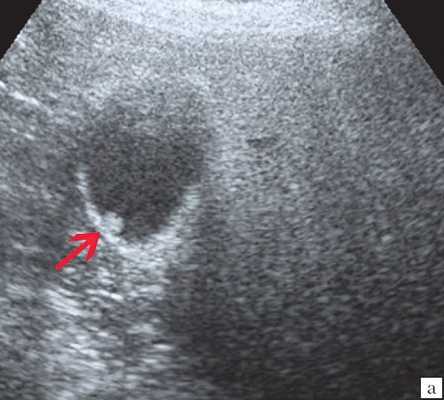

(Слева) На поперечной трансабдоминальной сонограмме в ямке желчного пузыря визуализируется эхогенная структура изогнутой формы с акустической тенью — изменения, характерные для «фарфорового» желчного пузыря.

(Левый) Пример полного кальциноза: у пациентки 67 лет, жалующейся на периодические боли в области желчного пузыря, при сканировании в черно-белом режиме в ямке желчного пузыря определяется тонкая гиперэхогенная полулунная линия, отбрасывающая плотную акустическую тень.

(Правый) У этой же пациентки в той же области в правом верхнем квадранте ожидаемо определяется диффузная криволинейная линия кальциноза, повторяющая контуры желчного пузыря.